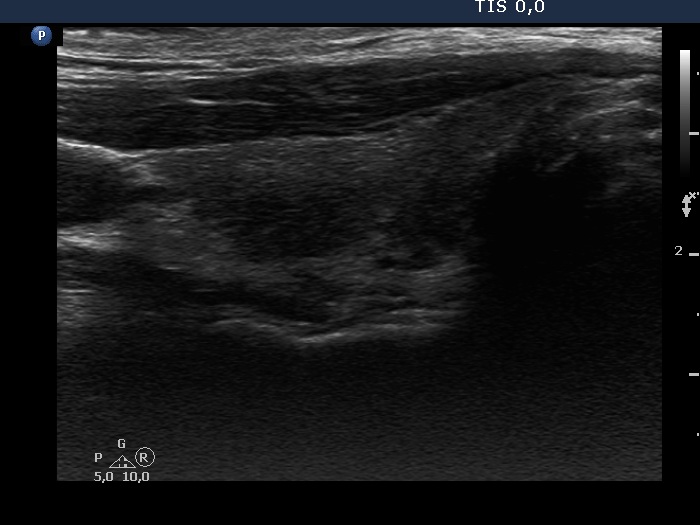

Second examination 14 months after the initial (4th row of images):

Ultrasonography: The size of the thyroid decreased dramatically and became atrophic. The right lobe still presented a small deeply hypoechogenic area. In contrast with the first examination, the basic echo structure of the left lobe was not normal but moderately hypoechogenic. The vascularization was decreased and average, right and left lobe, respectively.